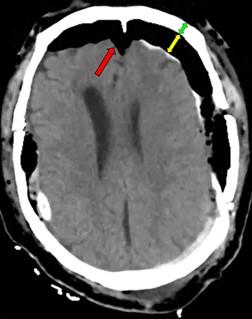

Evacuation of intracerebral hematomas by Neuroendoscopy: results in a series of cases

JERSON FLORES C.